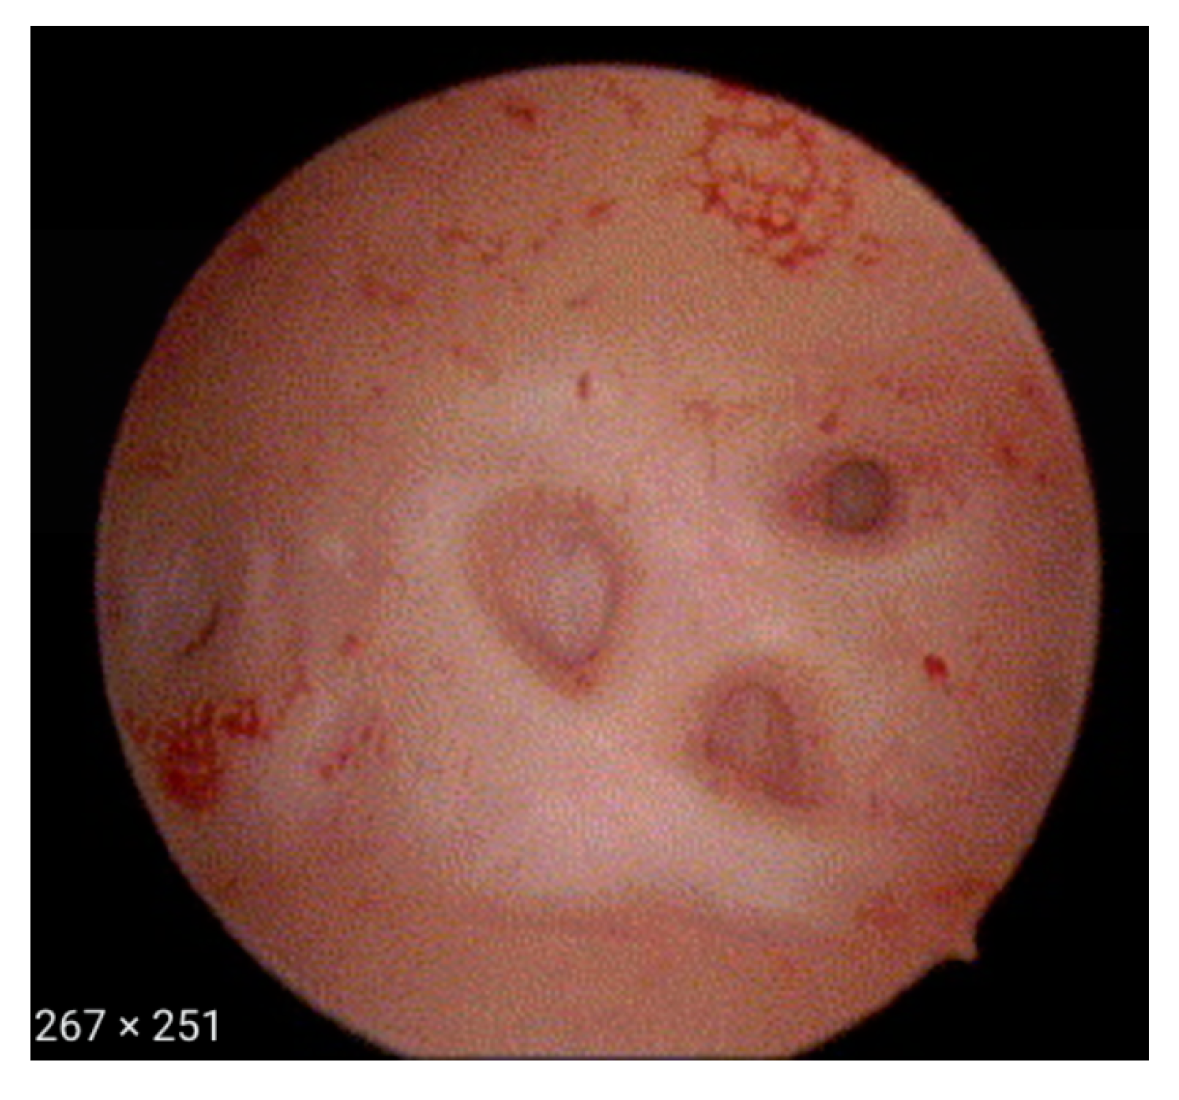

- Haemorrhagic cystic lesions presenting with a dark blue or chocolate brown appearance (Figure 5)